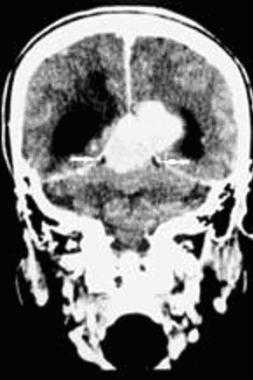

(Слева) МРТ, Т2-ВИ, корональный срез: у мужчины 47 лет определяется внемозговое образование однородной структуры с четкими контурами с минимальным отеком.

(Справа) МРТ, постконтрастное Т1 -ВИ, аксиальный срез: у этого же пациента визуализируется интенсивное относительно однородное контрастное усиление. Обратите внимание на компрессию треугольника левого бокового желудочка. Несмотря на отсутствие агрессивных рентгенологических признаков при хирургической резекции и гистологическом исследовании была диагностирована злокачественная Менингиома grade III. Для окончательного установления гистологического типа и степени злокачественности менингиомы необходима биопсия.